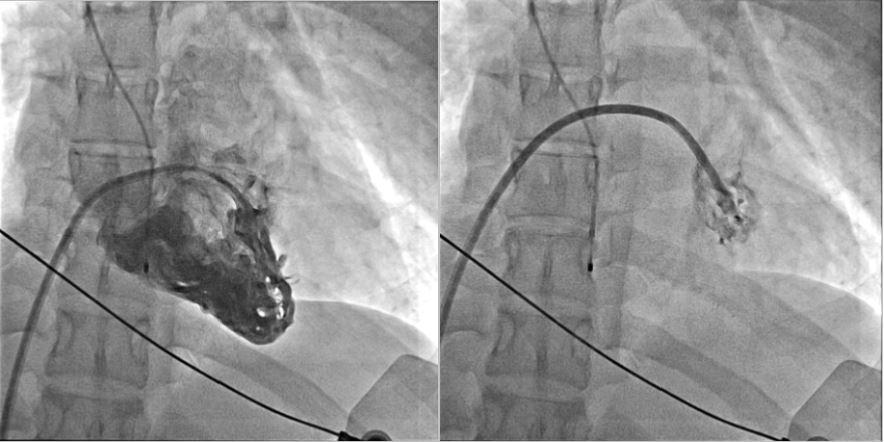

Coronary Angiography:

LM: Patent

LAD: Patent

LCX: Patent

RCA: Patent

**STEP 1: DiagnosticCAG**Puncturedright EIA; placed 6Fr sheath.EngagedLCA with 5Fr JL4 catheter, showing patent LCA, and with 5Fr JR4 for RCA,showing patent RCA.

**STEP 4: Insert ABIOMED Impella CP® Microaxial Flow Catheter for Cardiogenic Shock** Pre-embedded 2 Abbott Perclose ProGlide™ SMC System sutures at right EIA sheath. Inserted Impella sheath; Advanced 0.18 wire to LV with pigtail, and checked Impella CP device for function and primed with saline. Positioned Impella tip in LV using fluoroscopy; removed guidewire and connected to console. Confirmed Impella function; secured access site.

**STEP 4: Insert ABIOMED Impella CP® Microaxial Flow Catheter for Cardiogenic Shock** Pre-embedded 2 Abbott Perclose ProGlide™ SMC System sutures at right EIA sheath. Inserted Impella sheath; Advanced 0.18 wire to LV with pigtail, and checked Impella CP device for function and primed with saline. Positioned Impella tip in LV using fluoroscopy; removed guidewire and connected to console. Confirmed Impella function; secured access site.